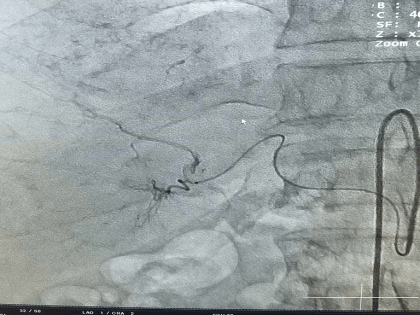

Амурские хирурги впервые провели уникальную операцию на печени

Благодаря успешно освоенной методике лечения рака печени амурские хирурги выполнили важную манипуляцию для пациента.